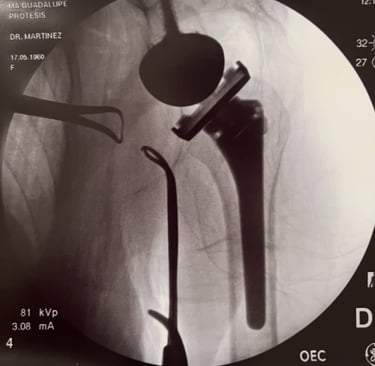

Control de radiografía de prótesis reversa de hombro.